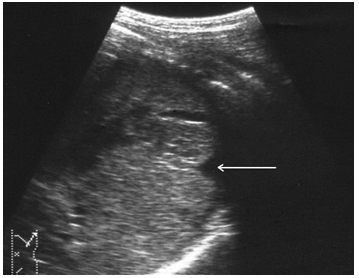

Чрескапсульные разрывы селезенки манифестируют нарушением непрерывности контура органа и визуализацией внутриорганных линий разрыва (рис. 7). Последние представляют собой гипоэхогенную или эхонегативную, в зависимости от времени, прошедшего после травмы, зону линейной или «ветвистой» формы с неровными и нечеткими контурами. Важно отметить, что прямые эхографические признаки, будучи патогномоничными для данного вида повреждений, не имеют облигатный характер. В частности, нарушение непрерывности контура селезенки наблюдается только у 25,4 % больных, а линия внутриорганного разрыва визуализируется в 60,3 % случаев. При этом возможность выявления указанных признаков в ранние сроки весьма проблематична и становится реальной только через 16–24 часа после травмы.

Рис. 7. Эхограмма чрескапсульного разрыва селезенки. Нарушение непрерывности контура указано стрелкой.